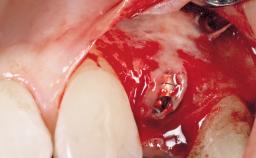

Late Flapless Placement of an Implant in a Maxillary Left Central Incisor Site

A 39-year-old male patient presented with a chief complaint of discomfort and gingival discoloration around his maxillary left central incisor. He was in good general health and was a non-smoker. His past dental history was significant because of the traumatic fracture of tooth 21 in a sporting accident at age 13. Initial dental treatment included endodontic therapy and a full-coverage restoration. The patient became symptomatic 5 years later, when structural failure of the tooth resulted in the dislodgment of the crown. Endodontic retreatment, apical surgery, and post-and-core restoration were performed.

Bone Augmentation Horizontal|Staged

Bone Volume Deficient horizontally, requiring prior grafting